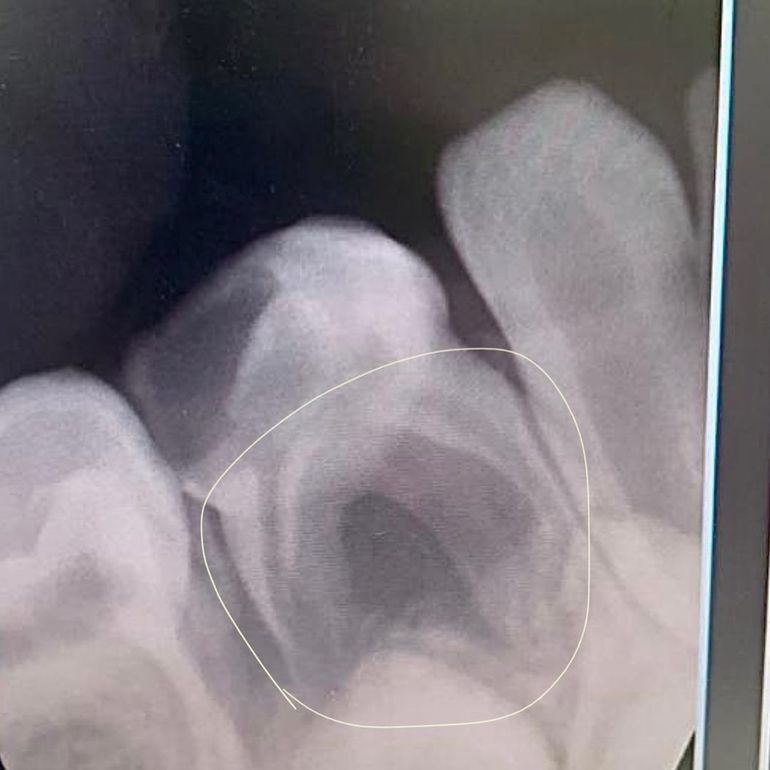

🔻Было сильное воспаление, образовалась кистогранулема - гнойный мешочек, который мог бы разрушить зачаток постоянного зуба. Медлить было нельзя и зуб пришлось оперативно удалить.

☝️На первом фото хорошо видно, что очаг воспаления был обширным. Под молочным зубиком можно заметить зачаток постоянного, с которым и граничило воспаление.